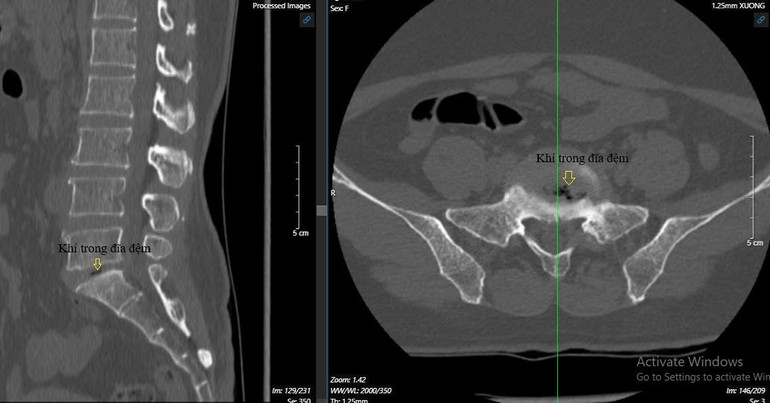

Bệnh nhân đến Bệnh viện Đại học Y Hà Nội khám và chụp X-quang, cộng hưởng từ phát hiện thoát vị đĩa đệm L5S1 trung tâm lệch trái lớn và có khí trong đĩa đệm L5S1. Điện cơ có hình ảnh tổn thương rễ thần kinh.

Tuy nhiên, bệnh nhân này có khí trong đĩa đệm nên cần phải thay đĩa đệm bằng miếng ghép và cố định cột sống.

Bệnh nhân này có khí trong đĩa đệm nên cần phải thay đĩa đệm bằng miếng ghép và cố định cột sống.